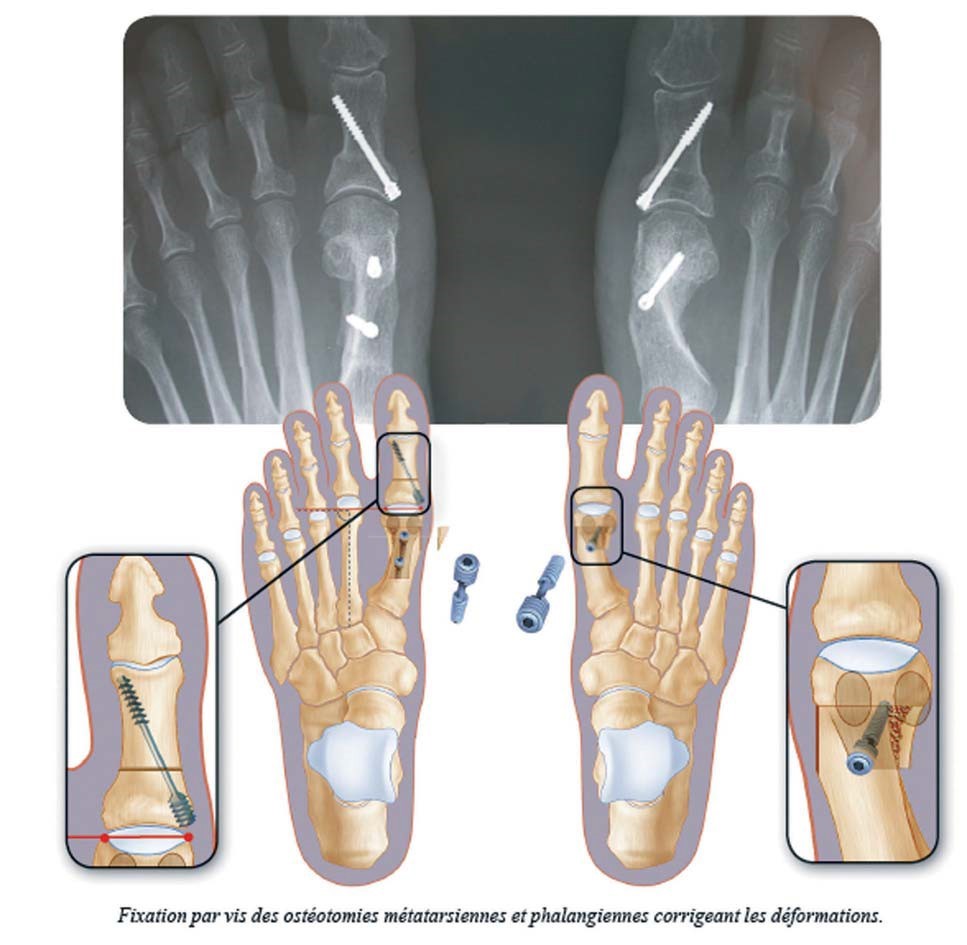

L’objectif n’est pas seulement de « raboter la bosse », mais de réaxer le métatarse.

• L’Ostéotomie : Le chirurgien réalise des coupes osseuses (ostéotomies) pour redresser le métatarse et la phalange. Ces corrections sont fixées par des petites vis qui restent généralement à vie.

• Les gestes associés : Si nécessaire, le chirurgien corrigera dans le même temps les griffes d’orteils ou les douleurs plantaires.